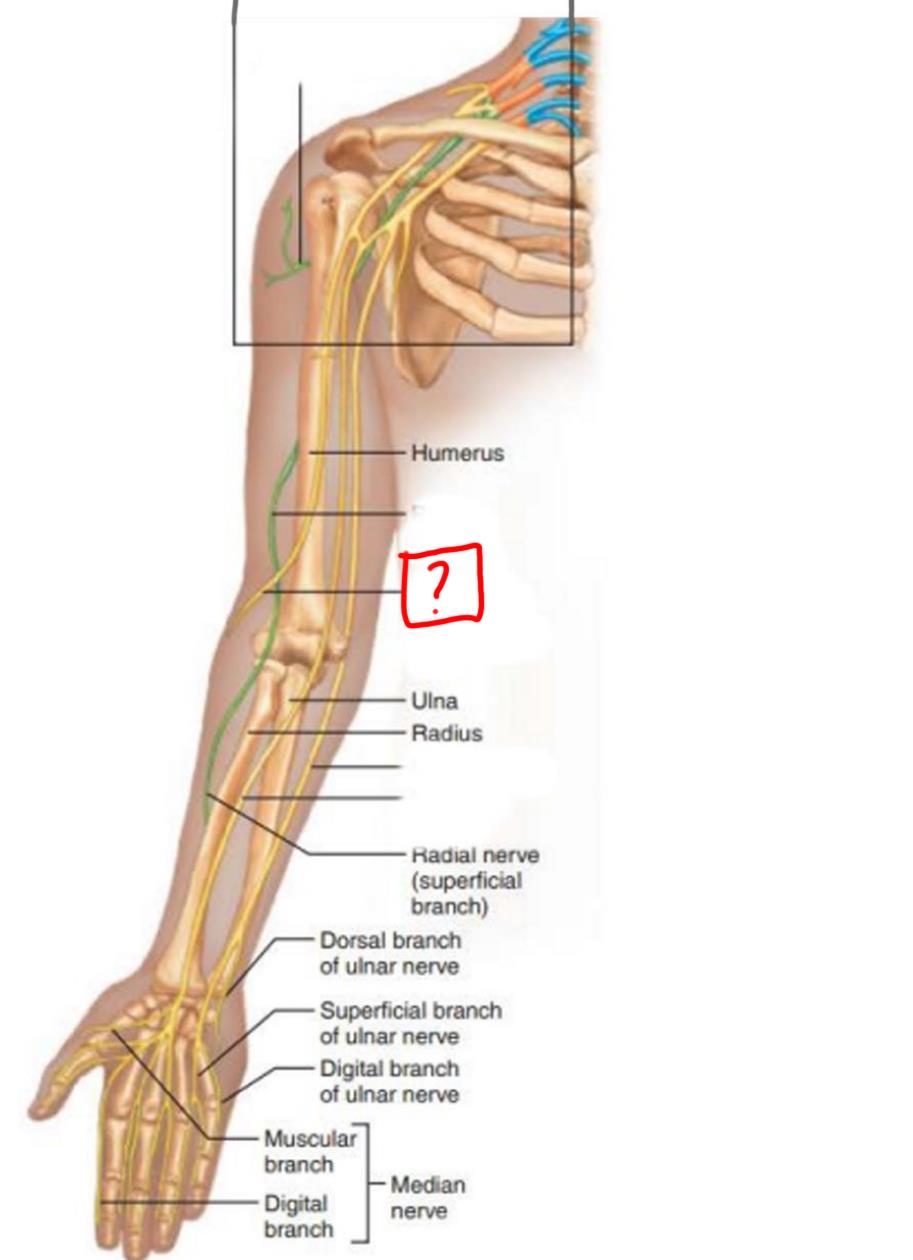

radial nerve

ulnar nerve

median nerve